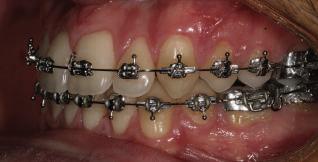

20 Dental Tribune Bulgarian Edition / октомври 2022 г. П ациентите със завършен растеж и скелетни проблеми обикновено представляват предизвикателство за ортодонт ската практика. Необходимостта от изваждане на зъби в комбинация с особеностите на възрастовата ортодонтия изисква особено внима ние. Фокусът върху критично важното значение на позицията на долните резци във връзка с дългосроч ната стабилност и постигането на оптимални оклузални взаимоотношения при затварянето на екстракционните пространства лесно може да излезе извън контрол. Когато към тези чисто кли нични проблеми се добави и стресът от натоваре ната практика, предизвикателството става още по-голямо. Всички тези фактори налагат използ ването на доказан подход с ясни и последовател ни стъпки, в което се разкрива силата на дисциплината „Алекзандър“ – предвидим протокол през целия процес на елиминиране на ротациите, ниве лиране на дъгите, затваряне на екстракционните пространства и финализиране на случая. Именно такъв е и случаят, който презентираме –екстракционен, скелетен клас 3 при възрастен па циент, лекуван по системата „Алекзандър“. ПРЕДВИДИМИ РЕЗУЛТАТИ ПРИ ПАЦИЕНТИ СЪС ЗАВЪРШЕН РАСТЕЖ И СКЕЛЕТЕН КЛАС 3, ИЗПОЛЗВАЙКИ ЕКСТРАКЦИОННО ЛЕЧЕНИЕ ПО ДИСЦИПЛИНАТА „АЛЕКЗАНДЪР“ Д-р Радой Димитров, България Преди започване на лечение клиничен случай | ортодонтия Фиг. 1а–1e Преди започване на лечение. Пациентът пристига в практиката с основното оплакване от невъзмож ност за нормално дъвчене. Снета е цялата необходима диагностична ин формация. Фиг. 1f–1h Снимки в профил и анфас. Фиг. 1i–1k Панорамна снимка, телерентгенография и анализ на телерент генография. Фиг. 1а Фиг. 1d Фиг. 1f Фиг. 1g Фиг. 1h Фиг. 1e Фиг. 1b Фиг. 1c Фиг. 1i Фиг. 1j Фиг. 1k

closed.

21Dental Tribune Bulgarian Edition / октомври 2022 г. ДИАГНОСТИЧНИ РЕЗУЛТАТИ: 1. Възраст на пациента: 21 години 2. Скелетен клас III (ANB 0) 3. Зъбен клас 3 4. Ръбцова захапка във фронта, кръстосана в дисталните участъци 5. Тясна горна челюст 6. Overjet – 0 мм, Overbite – 0 мм 7. Несъответствие на горната с долната средна линия 8. Единични контакти в ЦО 9. Хиподивергентен тип на растеж SN/MP – 33.5 10. Неравен гингивален контур 11. Неравна линия на усмивката 12. Тенденция за рецесии в долен фронт ПРЕПОРЪЧИТЕЛНО ЛЕЧЕНИЕ: Пълно ортодонтско лечение с метални брекети „Алекзандър“ Корекция на клас 3 захапката в областта на кучешките зъби с екстракция на първите пре молари в долна челюст Корекция на кръстосаната захапка в дистални участъци Коригиране на ръбцовата захапка във фронта Подобряване на ОJ и OB на пациента Стрипинг в долен фронт Подреждане на зъбите в горната и долната челюст Професионално хигиенизиране и профилактични дентални прегледи са препоръчителни на всеки 6 месеца. 1-ви месец След 1 месец са залепени брекети в горната челюст – поставена е еластична дъга. 016 NiTi. В долната челюст са елиминирани ротациите, поставена е стоманена дъга. 016SS, закалена с ток, и еластична верижка за затваряне на пространствата. 3-ти месец В долната челюст е поставена трета дъга – 17 x 25 NiTi с къси лигатури и верижка

В горната челюст се затварят пространствата с дъга .016SS и верижка. 5-и месец На 5-ия месец след залепяне на брекетите в долната челюст е поставена стоманена дъга 16 x 22 SS с четвъртито сечение, омега луп и тай бек. В горната челюст е поставена дъга 17 x 25 NiTi. Поради липсата на стабилни оклузални контакти са поставени лингвални верижки в областта на моларите, за да се предотврати нежелана ротация на 7-ите зъби. 6-и месец На 6-ия месец от началото на лечението са екстрахирани долните първи премолари, поставена е дъга 16 x 22 SS със затваряща чупка teardrop. Чупката се активира всеки месец по 1 мм с чинч-бек. клиничен случай | ортодонтия СТЪПКИ НА ЛЕЧЕНИЕТО Начало на лечението Лечението започва с поставяне на апарат за бърза експанзия в горната челюст. През първия месец от лечението са направени 24 оборота на апарата за експанзия. Залепени са брекети в долната челюст, поставена е дъга 17x25 CuNiTi, като са предпи сани клас 3 ластици (1/4”,4 1/2 oz) по време на сън, за да се осигури контрол върху торка на долните резци. Фиг. 2а Фиг. 3a Фиг. 4a Фиг. 3b Фиг. 4b Фиг. 3c Фиг. 4c Фиг. 3d Фиг. 4d Фиг. 3e Фиг. 4e Фиг. 5a Фиг. 5b Фиг. 5c Фиг. 5d Фиг. 5e Фиг. 6a Фиг. 6b Фиг. 6c Фиг. 6d Фиг. 6e Фиг. 7a Фиг. 7b Фиг. 7c Фиг. 7d Фиг. 7e Фиг. 2b Фиг. 2c Фиг. 2d

Dental Tribune Bulgarian Edition / октомври 2022 г.22 клиничен случай | ортодонтия 14-и месец В горната и долната челюст са поставени последни стоманени дъга с омега луп и тай бек – 17 x 25 SS с четвъртито сечение. Назначени е ластик за средната линия в комбинация с клас 3 ластик (1/4”, 6 1/2 oz). Контролни рентгенографии 13-и месец Екстракционните пространства са затворени. Направена е контролна панорамна снимка за оценка позицията на корените. Взето е решение за презалепване на брекетите на 12, 22 и пръстените на 36 и 46. 21-ви месец Средната линия в горната и долната челюст съвпадат. Ластиците са спрени. Свалени са пръстените и брекетите в горната и долната челюст, зигзаг ластици не са използвани поради благоприятните оклузални взаимоотношения. Фиг. 11j Ортопантомография в края на лечението. Фиг. 11k Телерентгенография след края на лечението. Фиг. 11l Анализ на телерентгенографията след лечението. Фиг. 11m Последователност на дъгите в горната и долната челюст Фиг. 11n Суперимпозиция на PreOp и PostOp ортопантомографии. 10-и месец Затварянето на пространствата е предвидимо и контролирано, без да се отварят пространства в зъбната дъга. Фиг. 8a Фиг. 8b Фиг. 8c Фиг. 8d Фиг. 8e Фиг. 10a Фиг. 10b Фиг. 10c Фиг. 10d Фиг. 10e Фиг. 9a Фиг. 9b Фиг. 9c Фиг. 9d Фиг. 9e Фиг. 9f Фиг. 11a Фиг. 11f Фиг. 11j Фиг. 11l Фиг. 11m Фиг. 11n Фиг. 11k Фиг. 11g Фиг. 11h Фиг. 11i Фиг. 11b Фиг. 11c Фиг. 11d Фиг. 11e

Dental Tribune Bulgarian Edition / октомври 2022 г. 23клиничен случай | ортодонтия реклама Лечението е продължило 21 месеца. Проведено е домашно избелване с индивидуални шини. За автора: Д-р Радой Димитров завършва с отличие Факултета по дентална медицина към МУ–София през 2015 г. В продължение на 5 години работи в няколко водещи практики в София, като през 2019 г. заедно със своята съпру га д-р Траяна Димитрова основават собствена практика в гр. Гоце Делчев –Dimitrovi Dental Care. Посещава редица курсове за повишаване на квалификаци ята, но най-сериозен тласък в развитието на ортодонтската си практика получава след завършването на комплексната ортодонтска програма, воде на от д-р Иван Горялов, базирана на дисциплината „Алекзандър“ – система с повече от 50 години опит в целия свят. Д-р Димитров е член на Българския изследователски клуб „Алекзандър“. Взе ма участие като гост-лектор в симпозиума с международно участие The Power of the Alexander Discipline, който се проведе на 14–15.05.2022 г. С д-р Ди митров можете да свържете на тел. +359885 252 025. Заключение Представеният случай е ярък пример за възможностите и красо тата на дисциплината „Алекзандър“ – приложен е утвърден под ход с ясни правила и са постигнати очакваните цели. Резулта тът ще бъде дългосрочно стабилен, тъй като са спазени всички правила, които се отнасят към максимално комфортната пози ция на зъбите в края на лечението. Постигнати са красива усмив ка и стабилна оклузия. ПОСТИГНАТИ РЕЗУЛТАТИ ОТ ЛЕЧЕНИЕТО 1. Коригирана ръбцова захапка 2. Коригирана клас 3 захапка в областта на ку чешките зъби 3. Коригирана кръстосана захапка в дисталните участъци 4. Коригиран овърджет и овърбайт 5. Разширена е горната зъбна дъга 6. Подредени зъби в горната и долната челюст 7. Постигната е стабилна захапка с множество контакти в ЦО 8. Драматично е подобрена дъвкателната функ ция 9. Подобрена е линията на усмивката ДРУГИ ПРОВЕДЕНИ ДЕНТАЛНИ ПРОЦЕДУРИ 1. Домашно избелване на зъбите 2. Екстракция на мъдреците Фиг. 12a Фиг. 12b Фиг. 12c Фиг. 12eФиг. 12d Фиг. 12f Фиг. 12g Информация за дати, цени и отстъпки www.bracescourses.com 0889 22 55 01 Практически курсове лектор д-р Иван Горялов Дисциплината „Алекзандър“ ПЪТЯТ КЪМ СУПЕРУСМИВКИТЕ 100% връщане на цялата сума, ако не сте удовлетворени след преминаване на Ниво 1 Директно и индиректно залепяне на брекети Анализ, диагноза и план на лечение Лечение на клас 2 дълбока захапка Екстракционно лечение Лечение на клас 3 отворена захапка НИВО 5НИВО 1 НИВО 2 НИВО 3 НИВО 4